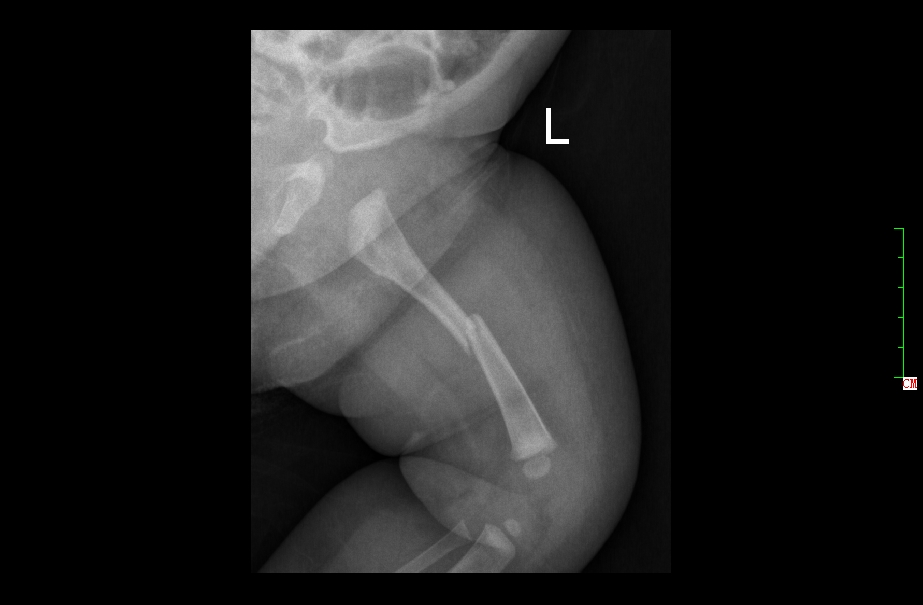

3月女婴股骨骨折正位片

3月女婴股骨骨折侧位片